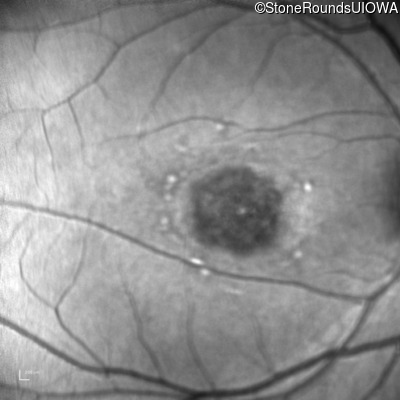

Infrared Fundus Photograph - Right - 20/125 -1

Exemplar